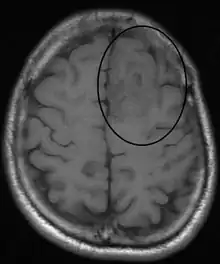

Oligodendroglioma arise mainly in the frontal lobe and in 50–80% of cases, the first symptom is the onset of seizure activity, without having any symptoms beforehand.[2] Headaches combined with increased intracranial pressure are also a common symptom of oligodendroglioma. Depending on the location of the tumor, many different neurological and neuropsychological deficits can be induced, including, but not limited to, visual loss, motor weakness, cognitive decline, and anxiety.[3] A computed tomography (CT) or magnetic resonance imaging (MRI) scan is necessary to characterize tumor size, location, and hetero- or homogeneity. Final diagnosis relies on biopsy and histopathologic examination of the tumor mass.[2]